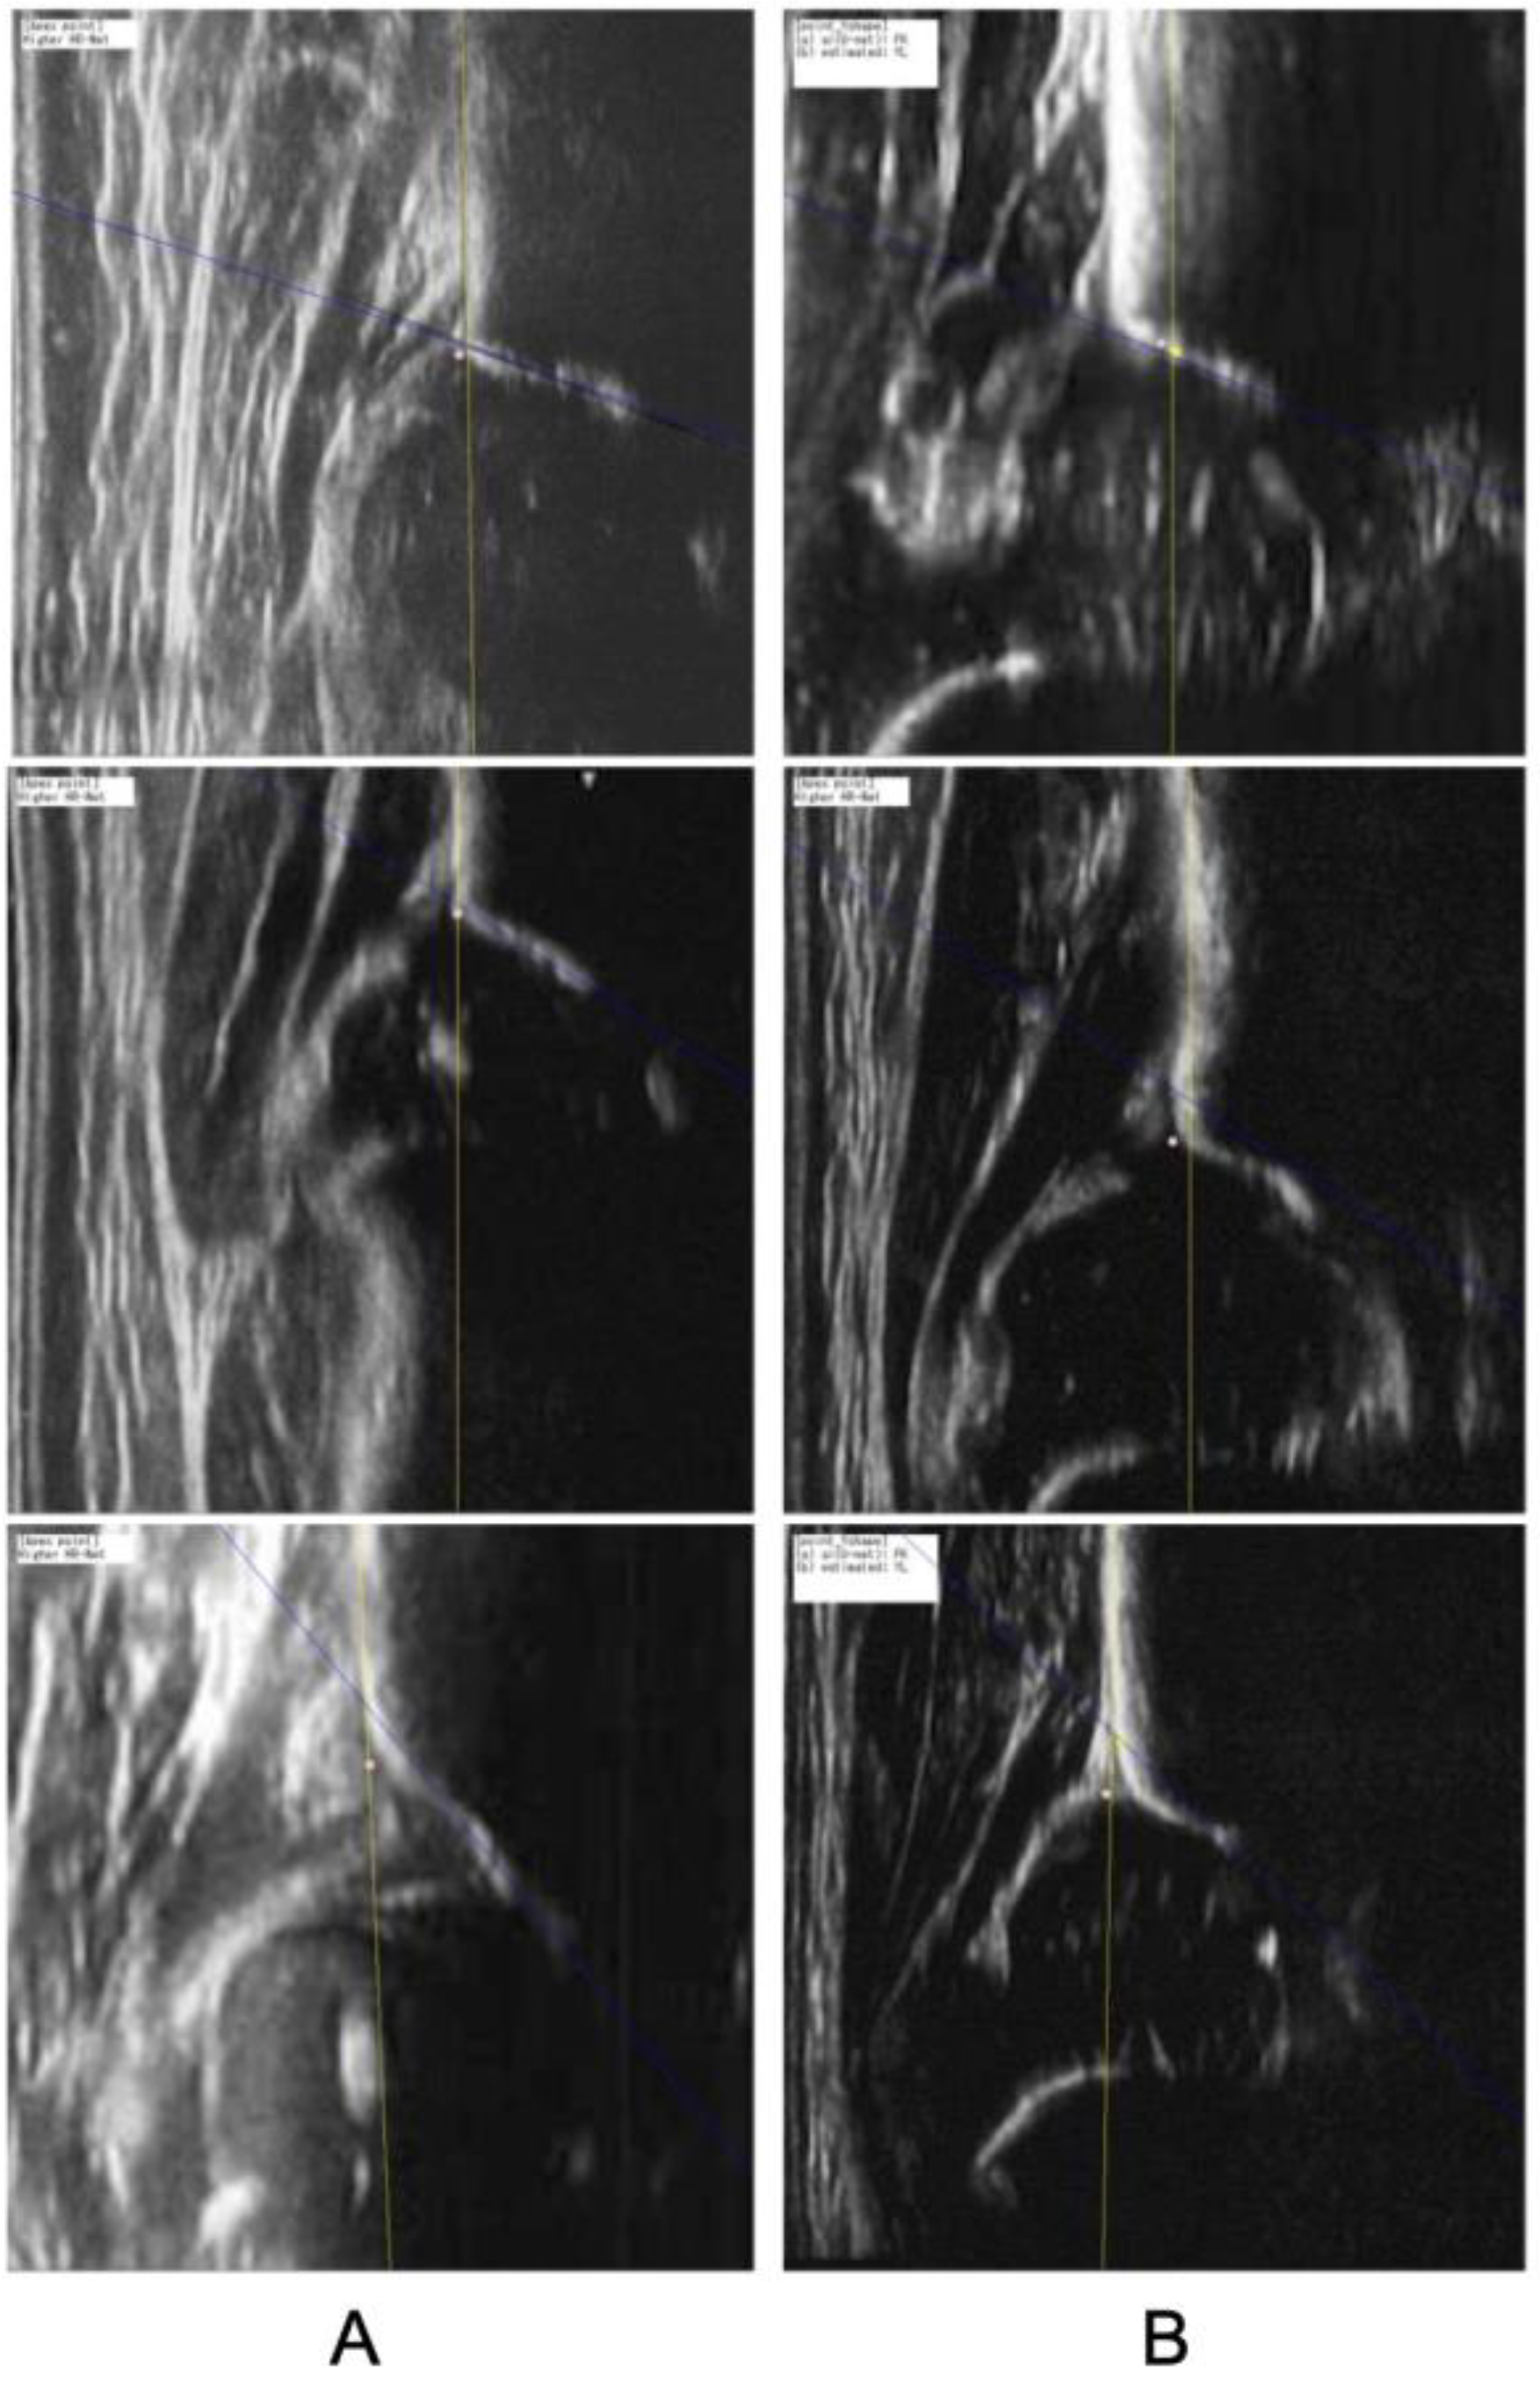

2.3.3. Generation of the Alpha Angle

3.3. Step 3: Accuracy of Detecting DDH in Qualified Images

4. Discussion